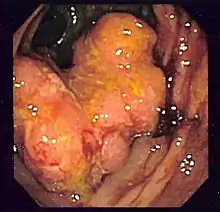

صورة تنظيرية لالتهاب كرون القولوني تظهر تقرح شديد.

تنظير القولون هو أفضل فحص لتشخيص مرض كرون، فهو يسمح بالرؤيا المباشرة للقولون والجزء الأخير من المعي اللفائفي، فبالتالي تحديد طبيعة المرض. في بعض الأحيان، منظار القولون يمكن أن يدخل إلى مكان أبعد من المعي اللفائفي، ولكن يختلف من شخص إلى آخر. أثناء العملية، أخصائي الجهاز الهضمي يقوم بأخد خزعة، أخد عينة صغيرة من النسيج للتحليل المخبري، والتي ممكن أن تساعد في التشخيص. بما أن 30% من مرض كرون يصيب المعي اللفائفي فقط، إقناء الجزء الأخير من المعي اللفائفي مهم للقيام بالتشخيص. العثور على توزيع شبيه بالرقع للمرض، متضمنا القولون أو المعي اللفائفي، لكن ليس المستقيم، قد يدل على مرض كرون، مثل السمات التنظيرية الأخرى.[4] استعمال الكبسولة التنظيرية للتشخيص للآن غير مؤكد.[101] مظهر "الحصوة" يرى تقريبا في 40% من الحالات المصابة بمرض كرون الذي يظهر في تنظير القولون، وهو عبارة عن مناطق من التقرح مفصولة بمناطق ضيقة من النسيج غير المصاب.